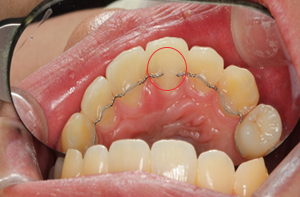

위 환자분은 교정치료 중 치아 우식이

발견되어 우식 치료를 의뢰받고 내원해 주셨습니다.

처음 내원해 주셨을 당시 근관치료가 되어있었던 상태였으며,

이때는 치아 변색은 없고 인접면 우식만 관찰되었습니다.

그 후 약 2년 뒤, 군 입대를 앞두고

치아가 변색되어 재방문 해주셨는데요.

현재는 교정 치료가 마무리된 상태였습니다.

육안으로 보기에도 한 눈에 앞니 변색이 확인되었습니다.

먼저 앞니 치료를 위해 치료 당일 치아를 최소로 삭제하되,

내부의 오염 물질을 확실하게 제거해 줍니다.

그 다음 치아 내부를 깨끗하게 정리하여

미백제를 치아 내부에 적용합니다.

그 후, 임시로 가봉하여 미백제가

치아를 밝게 만들어주도록 몇일 기다려줍니다.